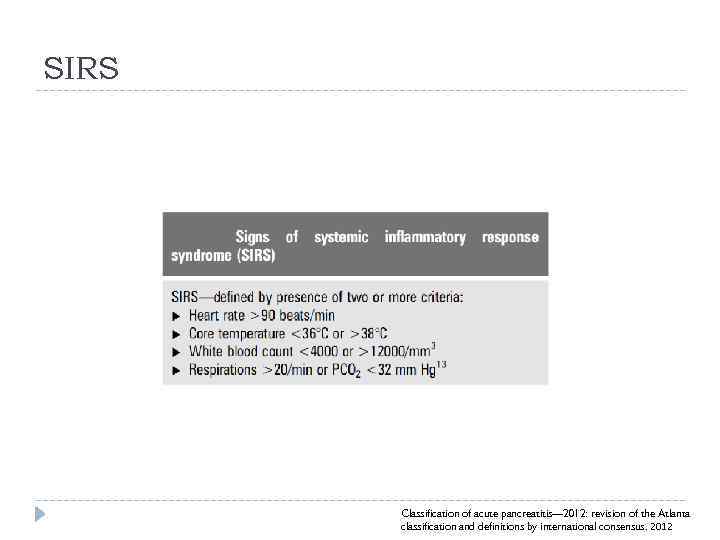

SIRS Classification of acute pancreatitis— 2012: revision of the Atlanta classification and definitions by international consensus. 2012

SIRS Classification of acute pancreatitis— 2012: revision of the Atlanta classification and definitions by international consensus. 2012